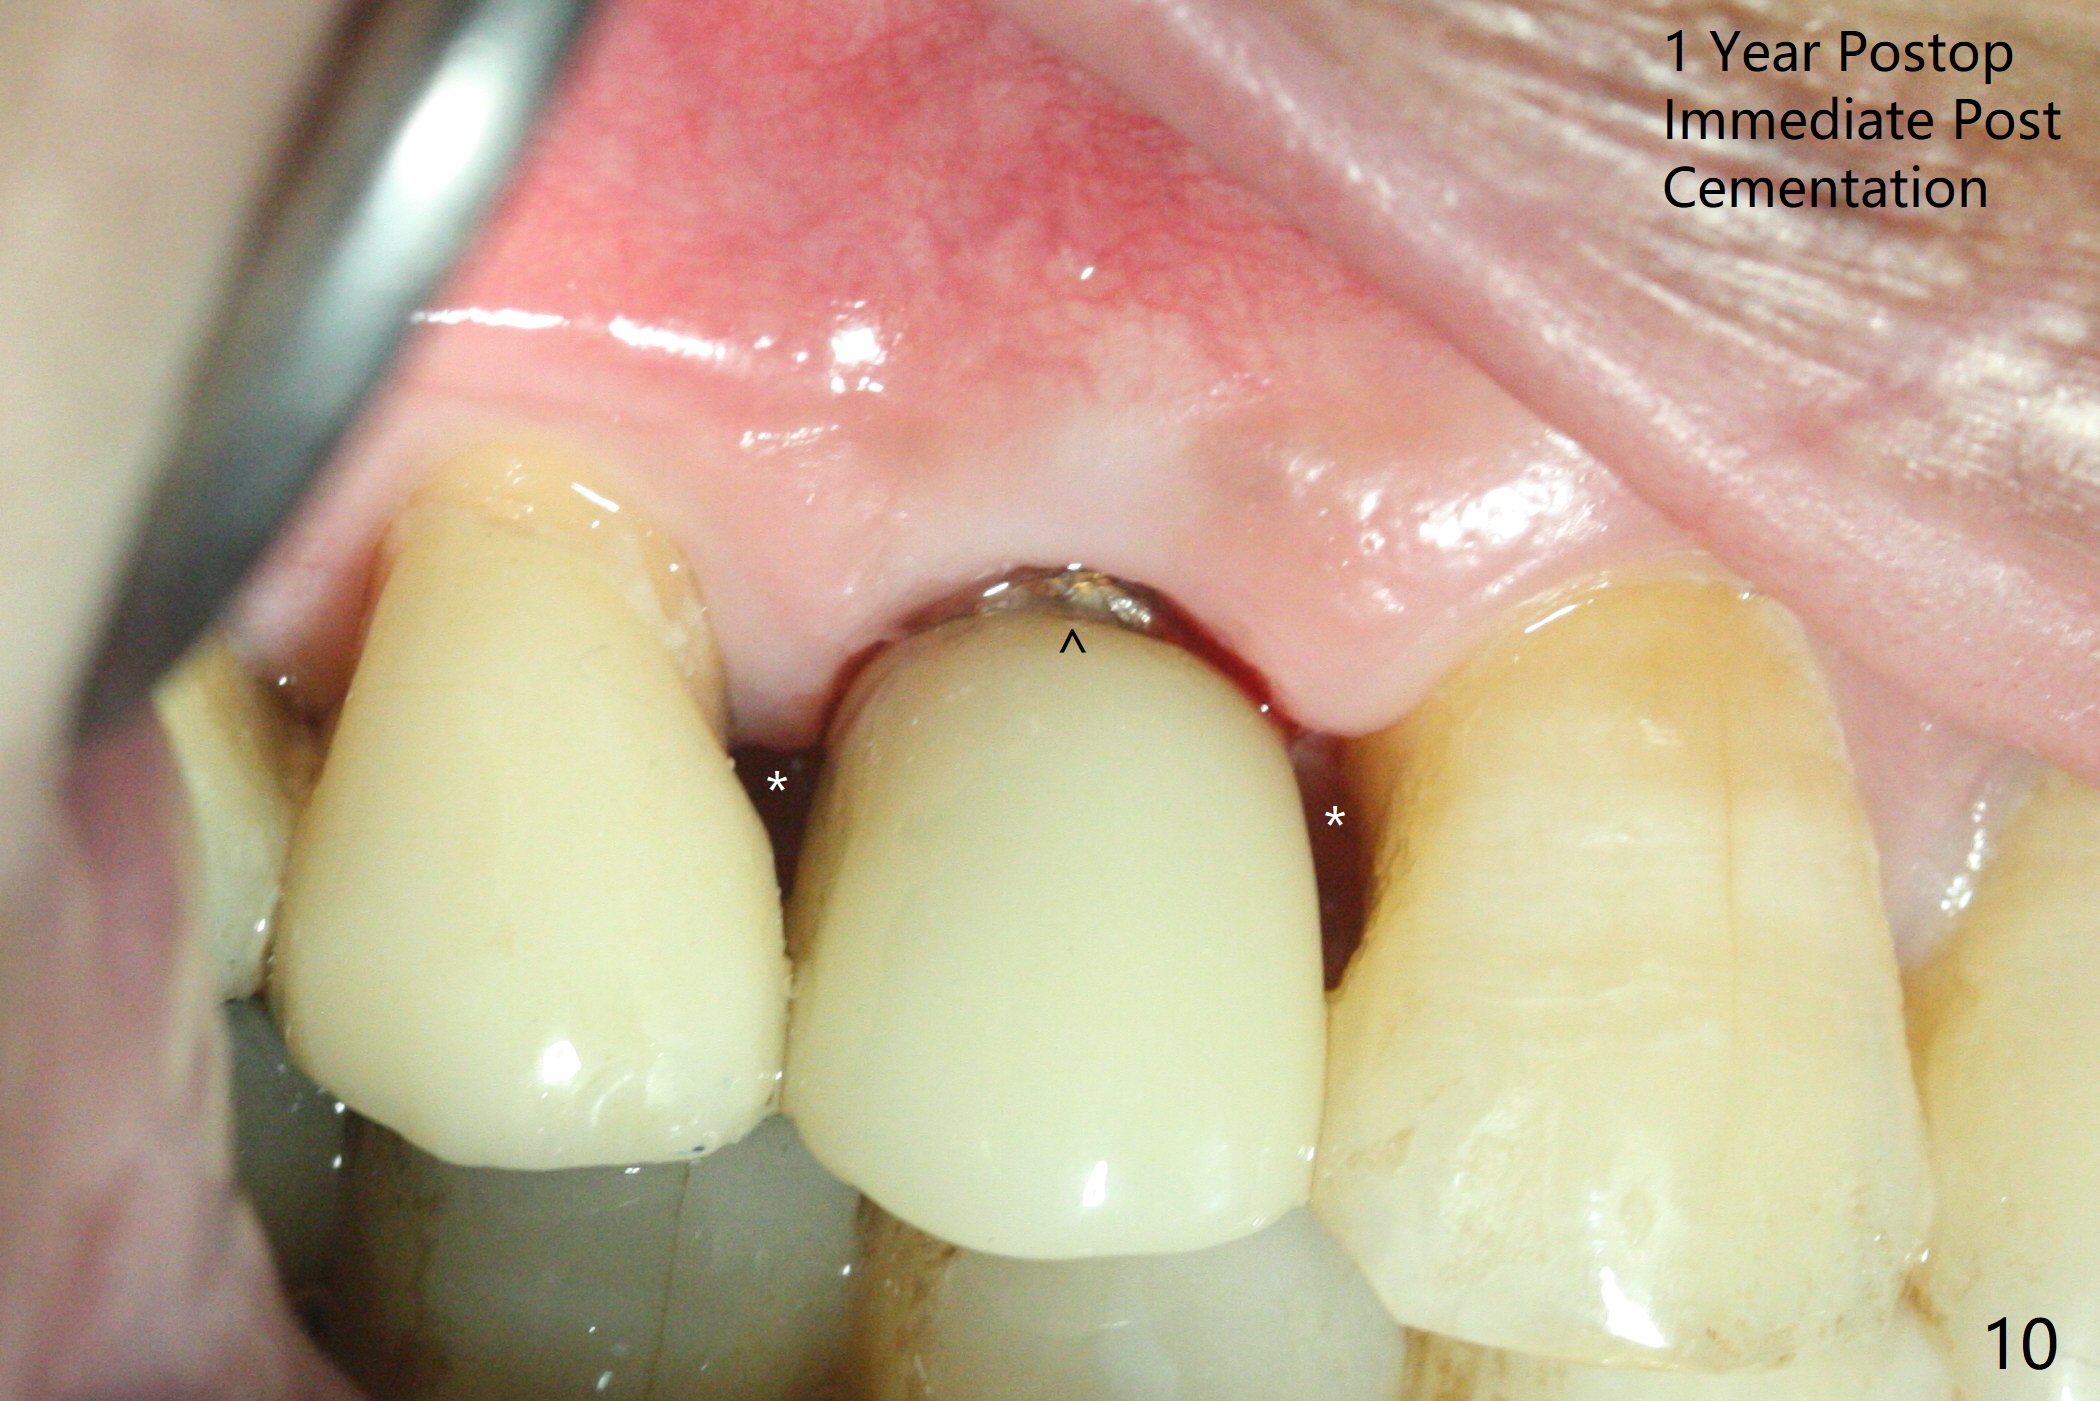

The buccal plate is normal at the tooth #5 (Fig.1) with the loose palatal fragment (Fig.2 P). Extraction leads to root fracture. Sectioning removes the palatal portion of the root and keeps the buccal semilunar piece (Fig.3 *); the mesiopalatal plate is resorbed (P). Initial osteotomy is off (Fig.4 (R: remaining root)). Redirection improves the trajectory (Fig.5). With the 2nd redirection (Fig.6 (4.5 mm tap)), a 4.5x12 mm implant is placed with 50 Ncm and sinus lift (Fig.7 black *); bone graft is placed with emphasis on the palatal defect (white *). As usual, an immediate provisional is fabricated. In fact the abutment may be not completely seated because of contact with the mesial crest. Prepare anesthetic and 5.5 mm profile drill. Take parallel BW or PA. Take occlusal photos to show no buccal or mesiopalatal atrophy. After 5.5 mm profile drill 11 months postop, the abutment has no contact with the mesial crest (Fig.8 <). Since the proximal contact between #3 and 4 is light with food impaction, the provisional at #5 is fabricated with tight distal contact. When the patient returns for final crown cementation (Fig.9), the food impaction is minimal between #3 and 4. The distal black triangle (Fig.10 *) and exposure of the abutment margin (^) are partially related to provisional fabrication and should dissolve over time considering socket shield.